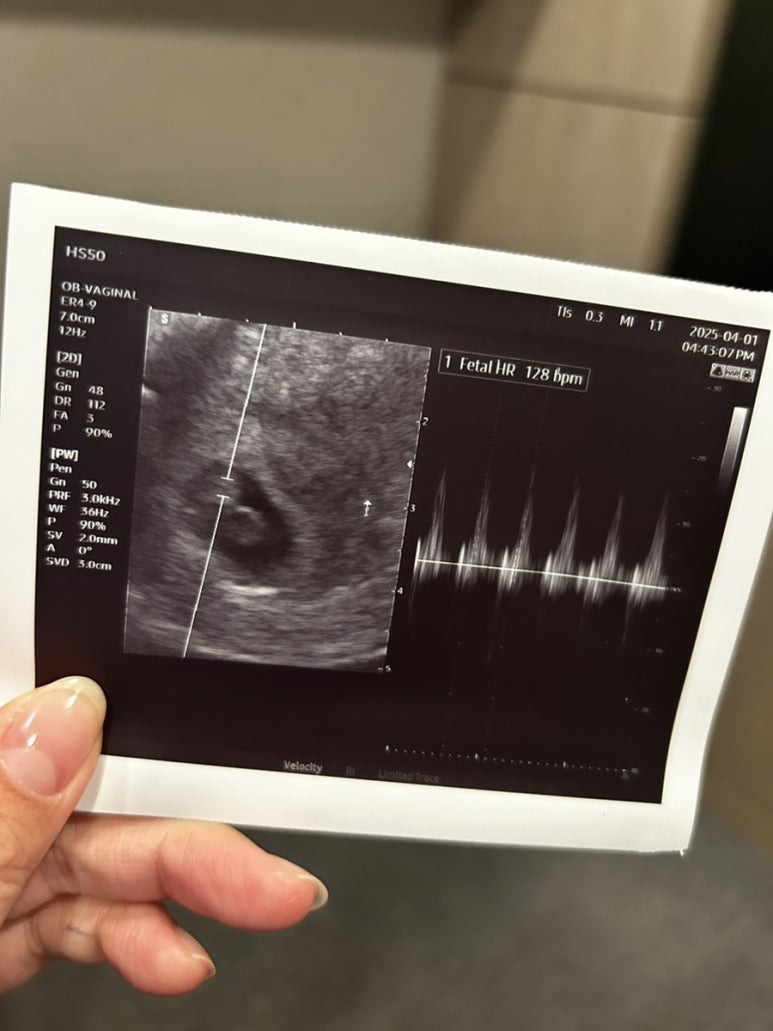

그리고 처음 들은 사탕이 심장소리

128bpm 으로 잘 뛰고있었다.

첫 심장소리 들을 때 운다는 사람들도 있는데

나는 눈물은 안났고,,

우리 사탕이 건강하게 잘 커주고 있다는 생각에

안심이 되었다.

애플산부인과는 마미톡이 없어서 영상저장은 없고,

사진으로 뽑아주셨다📷